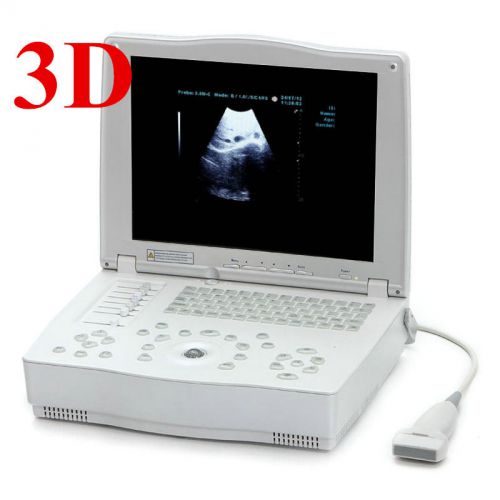

CE 15inch 3D+Portable Digital Laptop Ultrasound Scanner machine linear probe

CE 3D Portable Digital Notebook Laptop Ultrasound Machine Scanner System+2PROBES

10.4 inch Monitor PC 3D Ultrasound Scanner Machine + High Convex PROBE CE A++